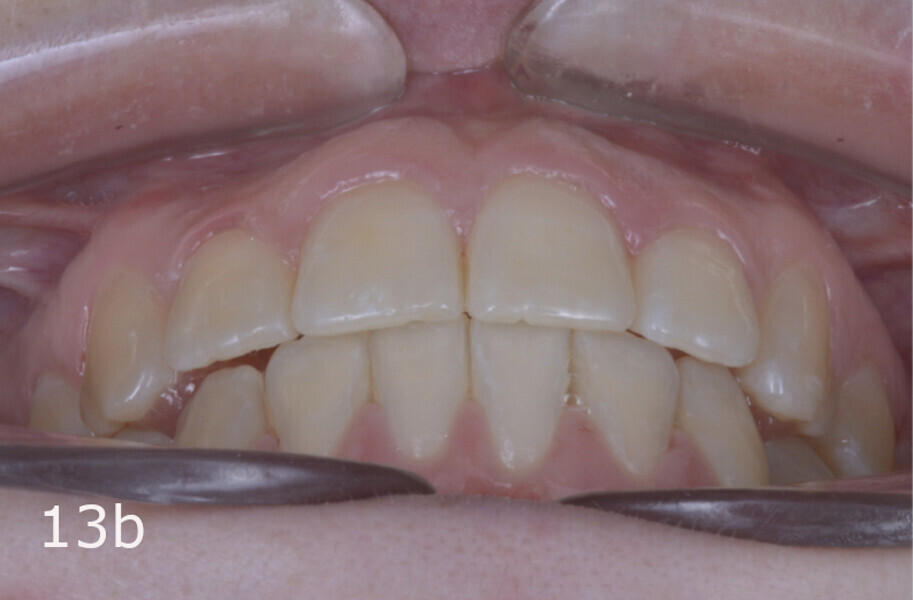

The total treatment time was 15 months. An Angle Class I relationship was established along with adequate anterior and canine guidance, establishing a functional occlusion. This not only ensures optimal masticatory function but also protects the teeth and the temporomandibular joint from excessive force. Maxillary and mandibular fixed retention were installed at the end of the treatment (Figs. 13–19).